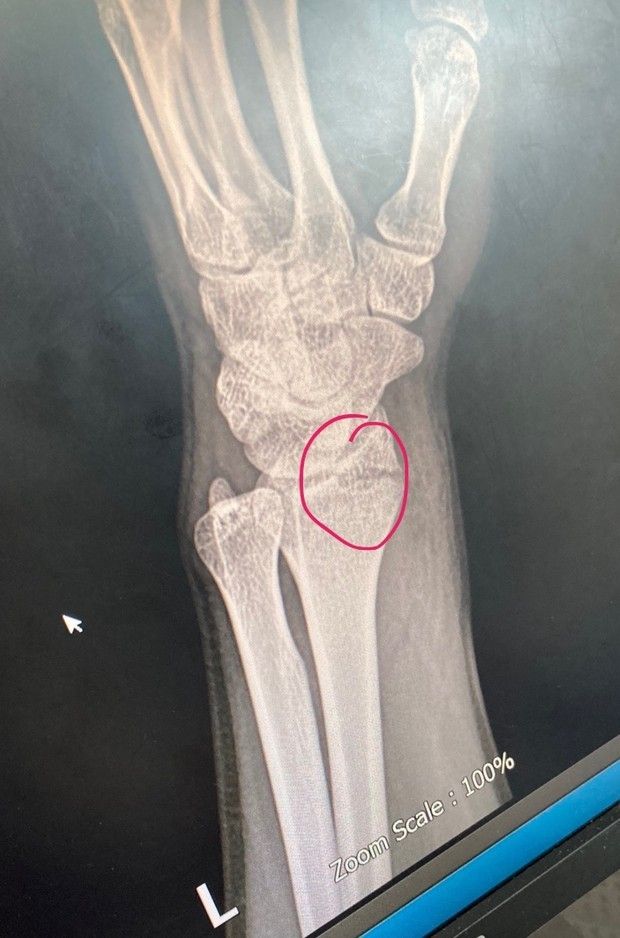

해당 사진은 엑스레이고요.

엑스레이 찍고 CT도 찍자해서 보니까

가로 골절에 세로 골절까지 있더라고요. ㅗ 모양처럼요.

현재 반깁스 상태고, 손목은 손바닥 방향으로 까딱은 되는데 다른 방향으로는 안 움직여요.

회전도 안되고, 붓기는 많이 빠진 상태입니다.

• 1번 째 사진